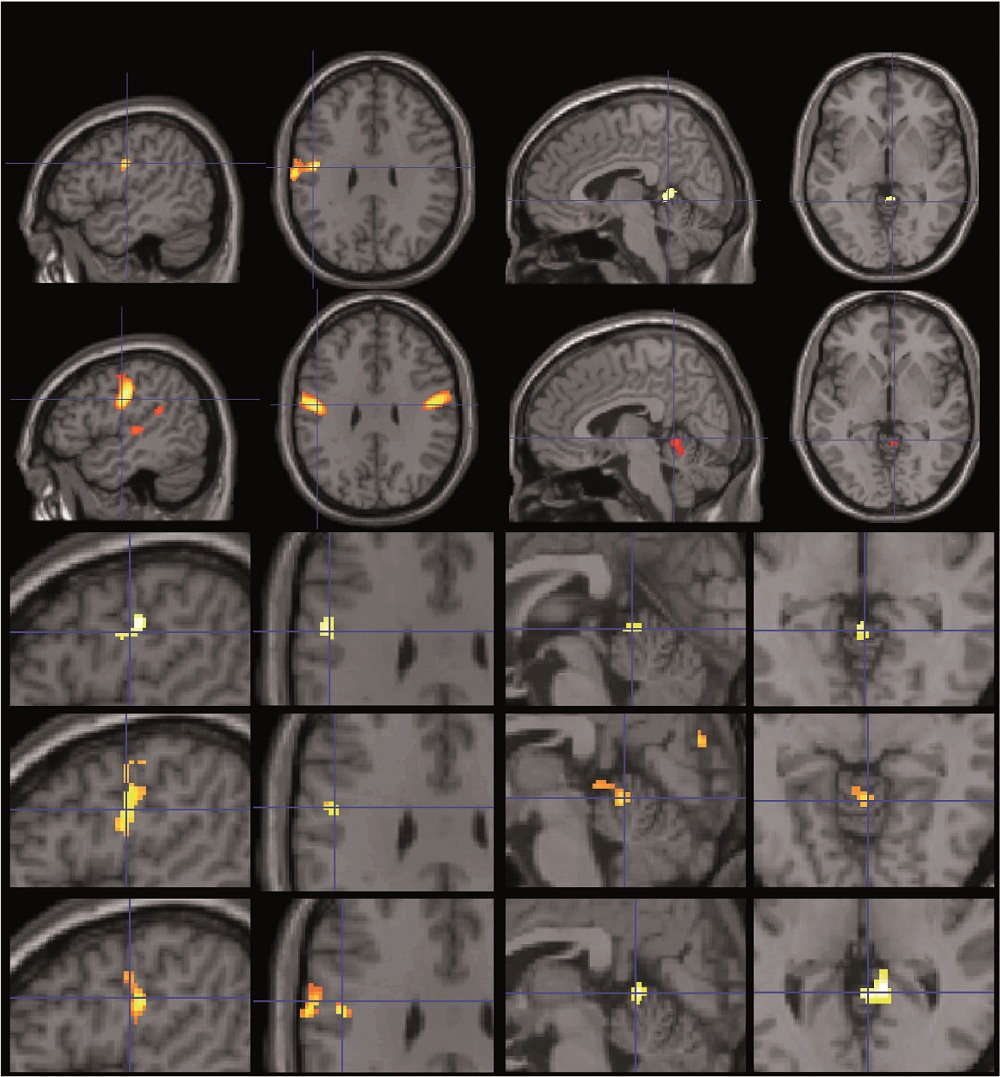

The researchers also saw that when participants' IQ levels either rose or fell in comparison with their peers, brain size in two regions also changed. When verbal IQ rose, brain structures activated by speech changed, and as nonverbal IQ changed, brain structures involved in finger movements changed.

They also saw these brain regions activated when the students had to perform verbal and visual tests, as well, so the researchers are pretty certain the brain areas are linked to these specific types of intelligences.

"The change in verbal performance was related to the change in brain structure in a region of the brain we know is involved in articulating and producing speech," Price told LiveScience. "In both cases the functional attributions of the regions were very consistent with what we were seeing in the IQ results."